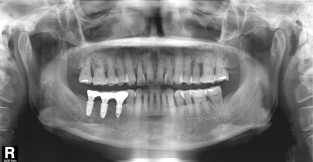

전체어금니

치료기간 : 2022-03-05 ~ 2022-10-01

1. 상기 x-ray 이미지 모두 동일한 해당 의료기관에서 진료한 환자입니다.

2. 상기 x-ray 이미지 모두 동일 인물의 것입니다.

3. 치료 전 이미지는 2022-03-05에 촬영했으며, 치료 후 이미지는 2022-10-01에 촬영하였습니다.

4. 상기 x-ray 이미지 모두 동일 조건에서 환자분의 동의를 받아촬영되었습니다.

* 임플란트 시술은 환자분의 상태(고혈압, 당뇨 등)에 따라 부작용이 있을 수 있으니, 반드시 전문의와 상담이 필요합니다.

* 임플란트 수술 부작용

: 수술 후 출혈, 교합, 통증, 붓기, 염증 등의 문제점이 발생할 수 있습니다.)